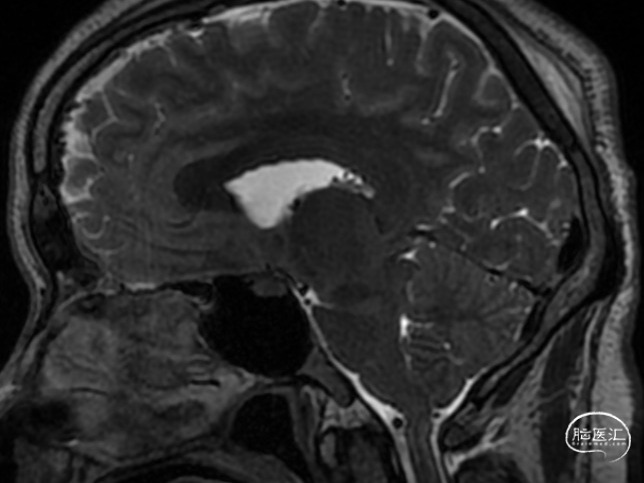

患者因“自发性双侧亚急性硬膜下血肿”收入功能神经外科,我科经过仔细全面检查,考虑诊断为“自发性低颅压头痛”并经MRI全脊柱水成像确定原因为寰枢椎之间有一处硬膜窦道,遂采用了精准微创的方法行C臂定位下硬脑膜漏口硬膜外血贴治疗术。术前患者一直卧床半月,术后第二天患者既症状明显改善下床活动,后患者治愈出院,未遗留神经并发症。2周后经MRI复查漏口已消失。本案例详细资料于2018.3.25日发表于《神外资讯》的 颅脑创伤-神经重症病例周刊(第59期)。

图7:2周后脊髓MRI水成像复查瘘口消失。

患者,女,36岁,因“头痛6天”入院于2002.5.19,入院后考虑“自发性低颅压头痛”,腰穿测压25mmH2O。行全脊髓MRI水成像未见异常,遂行全脊髓MRI造影术提示:颈1.2间左右两处瘘口分别位于颈1椎板上下缘。行DSA下精准靶向硬膜外血贴治疗后,患者第二天症状明显改善,第三天即痊愈出院。嘱患者两周后复查,因患者恢复满意,2周后患者不愿再做复查。